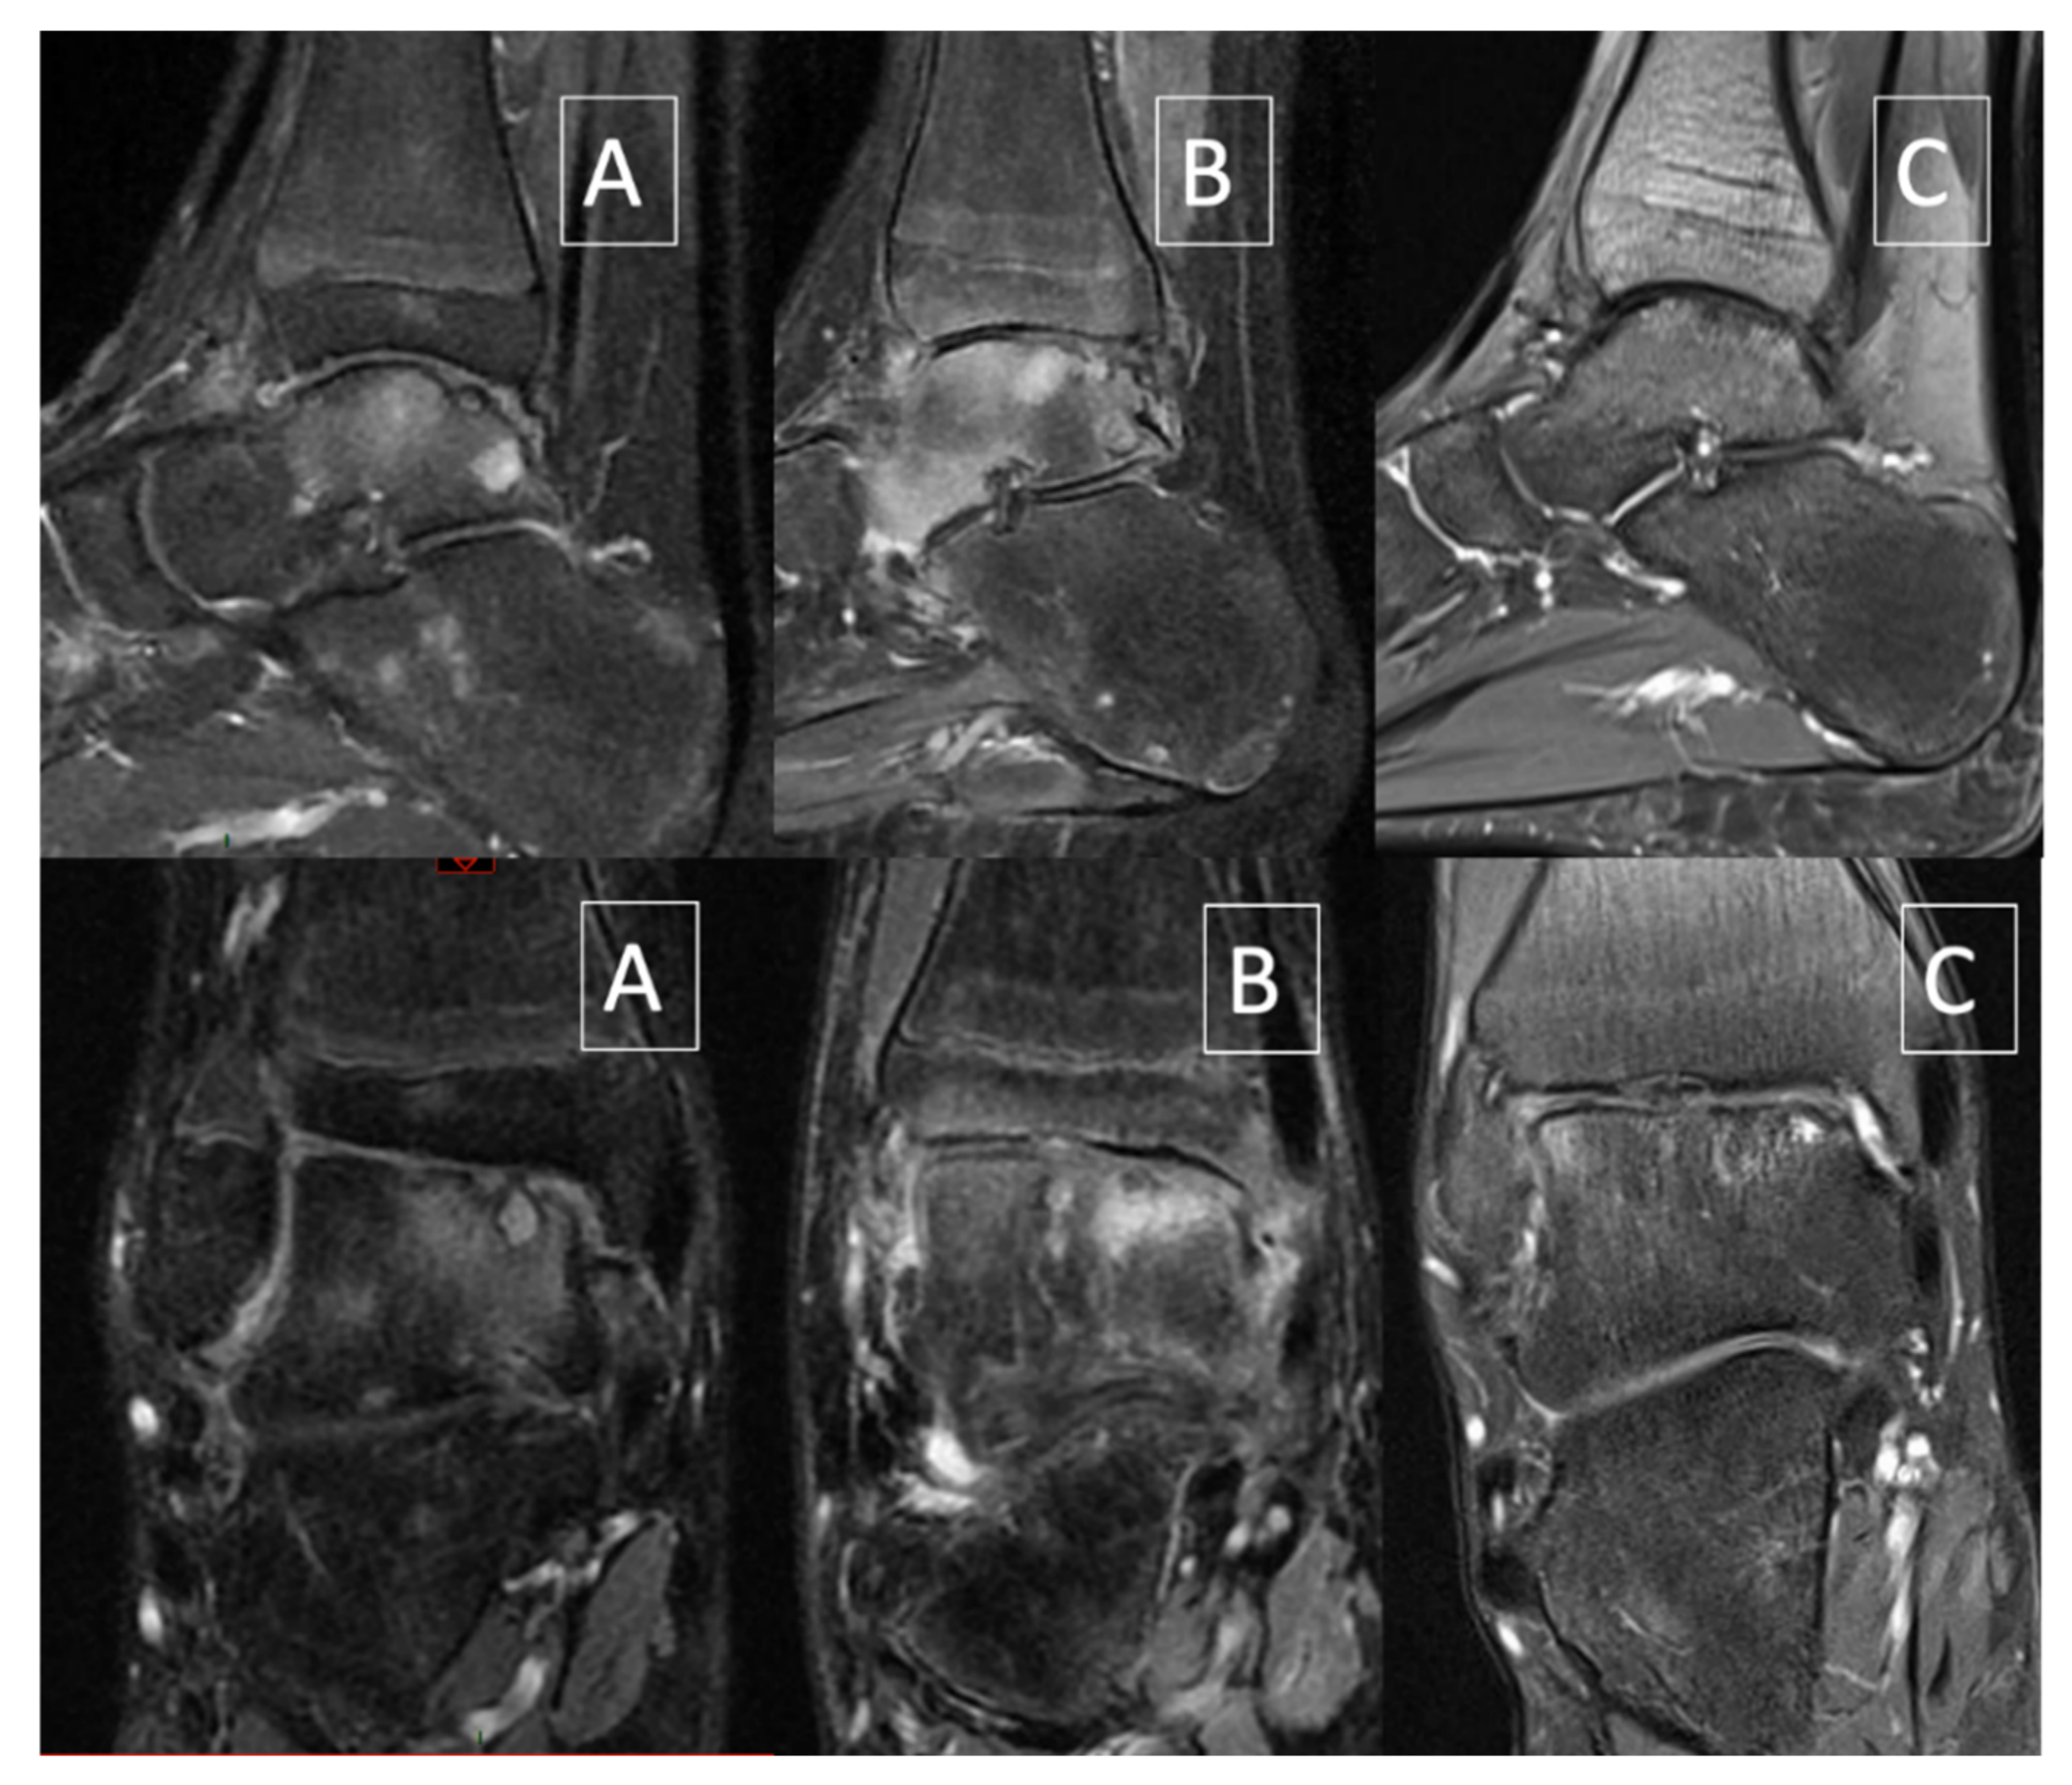

Figure 2. Sagittal and coronal fat-saturated proton density–weighted MRI. (A) June 2017 (4 months before ankle joint distraction): worsening of the cartilage lesion with collapse. (B) January 2018 (2 months after ankle joint distraction): edema with stable aspect of the cartilage lesion. (C) December 2019: decrease of edema and improvement of bony and cartilaginous lesions.

2. Case Report

The current case report describes clinical and biomechanical outcome measures of AJD in a 14-year-old patient with severe haemophilia A. He is a cooking school student (52 kg, 1.75 m) requiring being on his feet during classes, leading to many missed classes due to ankle and foot pain. He has a history of recurrent hip and right ankle hemarthrosis from age 12 onwards. He never developed inhibitors. He developed a target joint in the right ankle after age 12 despite adequate prophylaxis (standard rFVIII 35 IU/kg, three times a week). Since January 2016, at 14, the patient had significant pain in weight-bearing situation as well as recurrent hemarthrosis and suffered from increasingly frequent ankle hemarthroses with continuous diurnal and nocturnal pain. Initially, he received conservative treatment encompassing footwear, custom made foot orthotics and physiotherapy. Walking was only possible with crutches. Despite regular prophylactic treatment and a radiosynoviorthesis with ytrium performed on 29 April 2016, the patient still presented recurrent hemarthroses with significant anterior synovial hypertrophy. After anterior open synovectomy of the right ankle performed on 14 June 2016, the mobility of the ankle was satisfactory with 15° dorsi flexion and 20° of plantar flexion. Walking was normal and monopodal jumping is possible without pain. Despite the aforementioned conservative treatment, the MRI performed on 1 June 2017 showed worsening of the osteochondritis of the talar dome with loss of convexity and sinking of the cartilage surface (Figure 2A). Subsequently, a surgical synovectomy was performed by anterior arthrotomy. As a result, he no longer sustained any ankle joint bleeds, but the ankle joint remained painful despite daily use of Cox2-selective non-steroidal inflammatory drugs (NSAID) and daily rFVIII injections.

Distraction began the day after the surgery and was progressive at the rate of 1 mm/a day until 5 mm distraction. Post-operative care involved daily pin site dressings for the 10 first days with povidone-iodine and later with 70° alcohol. Weight-bearing was forbidden as long as the fixator was in place. The fixator was removed in January 2018 after 12 weeks and physiotherapy started immediately after. However, not long after removal, the patient developed a complex regional pain syndrome (CRPS) with nocturnal and weight-bearing pain, erythrocyanosis, paresthesia, and dysesthesia. He was treated with daily physiotherapy, anti-inflammatory, tramadol, and intra-articular injection of hexatrione. Diagnosis of CRPS was confirmed by MRI showing extensive bone edema (Figure 2B).

Shortly after this 1 year follow-up, the patient suffered a stress fracture of the third metatarsal bone of the right foot that healed uneventfully. In February 2019, the patient further improved and was able to walk and run without pain and MRI showed a stability of the chondral lesion (Figure 2C). Since June 2019, pain resolved completely and the patient could resume normal physical activities, including fitness three times a week. A second post-operative 3D gait analysis was performed at 18 months follow-up showing an early plantarflexion pattern at the ankle joint during midstance (Figure 3). This observation may illustrate an inhibited tibial advancement resulting in a premature heel rise during midstance. Since the clinical examination revealed a normal sagittal plane passive ankle range of motion together with a normal joint end-feeling, it was concluded that this deviated ankle joint motion pattern is part of a walking strategy in which high loading of the anterior talar joint surface is avoided. We also observed a tendency towards increased power absorption at the midfoot with peak power absorption of 1.2 Watt/kg, being almost two times higher when compared to boys of the same age. Since the latter (mal)adaptive compensations may cause overuse injuries at the foot and lower limb, the patient was advised to wear rocker-bottom footwear and custom-made foot orthotics.

From a hematological viewpoint, it can be stated that this procedure can be performed safely in patients with severe hemophilia A, provided accurate peri-operative FVIII substitution. From a structural point of view, this AJD was a success because it firstly improved and secondly stabilised the osteo-cartilaginous lesions of the ankle. Some structural lesions persisted; however, it is reasonable to assume that further deterioration of the joint was prevented and therefore also extended the timing of end-stage surgical interventions. Even though CRPS was developed after removal, the patient further improved and was able to walk and run without pain and MRI showed a stability of the chondral lesion (Figure 2C). The three cases of Van Meegeren and colleagues also showed structural improvement on MRI, however in case 3 AJD did not cause complete disappearance of bone oedema and of some of the subchondral cysts.